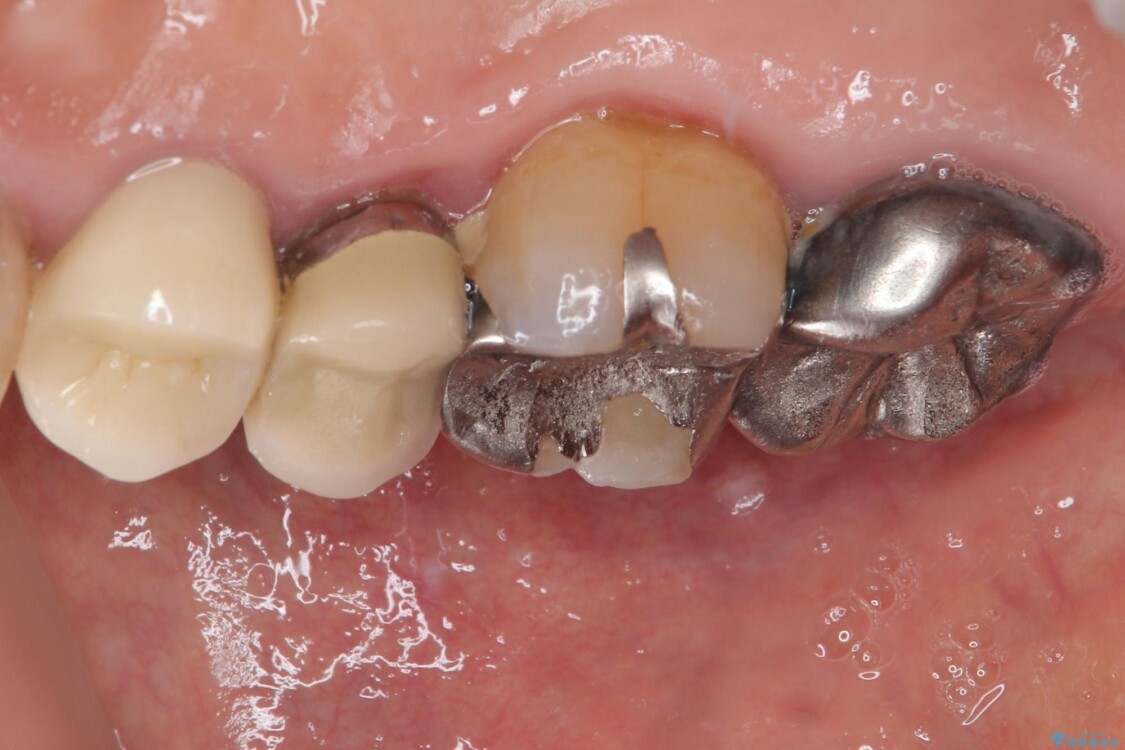

「以前治療した歯の被せものが外れてしまった」とのことで、右上の小臼歯の被せもの脱離を主訴に来院されました。

診察の結果、被せもの(クラウン)だけでなく、土台(コア)ごと外れてしまっている状態でした。根管治療済みの歯ではありますが、今回患者様のご希望により、根管治療の再治療は行わず、補綴処置のみを行う方針となりました。

治療前

• 自然な美しさと強度を両立!右上小臼歯の被せもの脱離に対する審美補綴治療 治療前画像